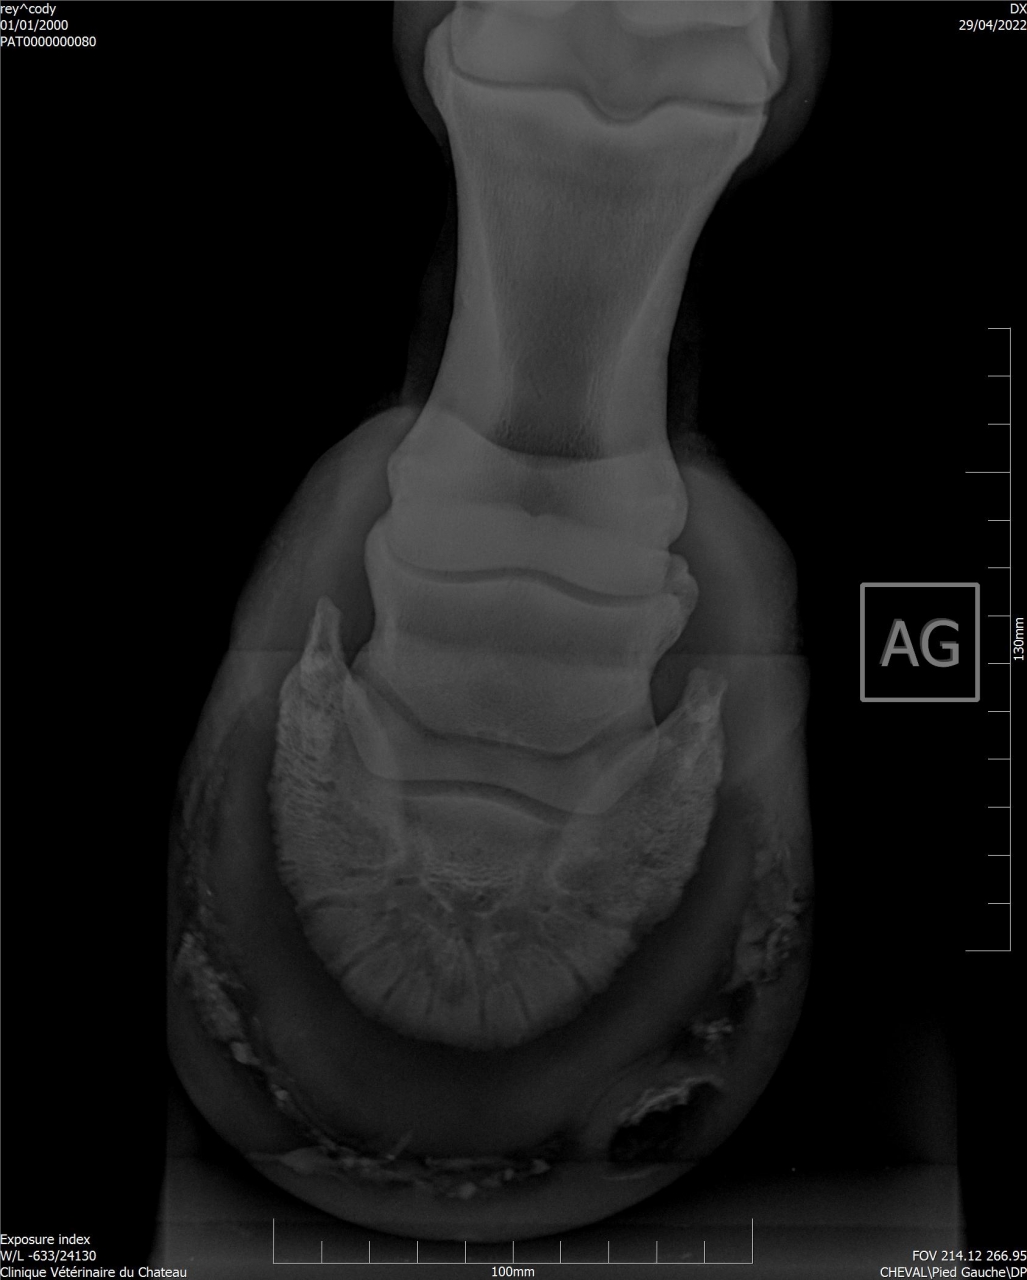

| Dire merci | Je remonte le post Mon cheval a été diagnostiqué naviculaire, il y a des fossettes synoviales. Ma véto préconise une infiltration avec du Tildren ou de l’Osphos. Aujourd'hui mon cheval a été ferré : antérieurs avec oignons et plaques en cuir, ferrure normale aux postérieurs. Voici les radios : ![]() ![]() ![]() ![]() ![]() |

| Dire merci | Les radios LM montrent une pince trop longue et pas de roll/ breakover Agir sur cela soulagera déjà énormément l’arrière du pied ! Sur la dp 60 on voit une zone noire circulaire Aurais tu une photos vue solaire stp ? Y a t’il fourmilière/évasement important voire un abcès récent ? |

| Dire merci | Je n'ai que ça comme radios ... Il y a des fourmilières aux 2 antérieurs. |